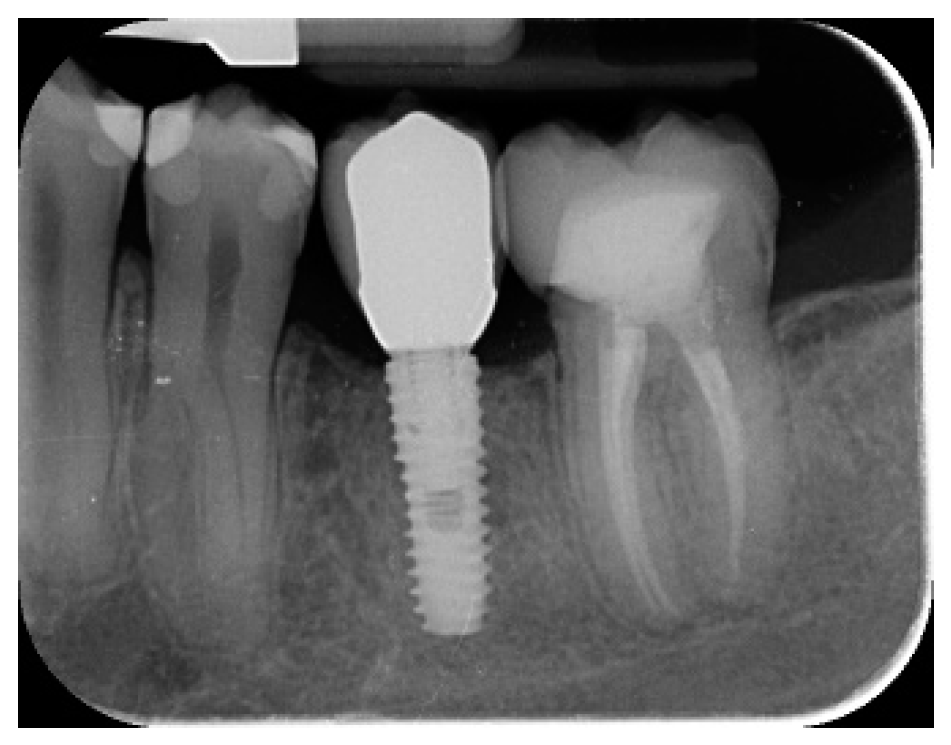

- Marginal bone level changes were assessed by digital periapical radiographs (Digora Optime; Soredex, Tuusula, Finland) using the parallel technique and commercially available film holders. Three time points were evaluated, at implant placement (baseline), immediately after the insertion of the restoration, and one year after loading. The averaged mesial and distal distances from the most coronal margin of the implant and the first bone-to-implant contact was measured to the nearest 0.01 mm and taken as the marginal bone level. The difference in levels between time points was taken as marginal bone loss (MBL).

- Horizontal bone augmentation was evaluated at the CBCT scans, 1 mm below the original bone crest. The volumetric data were superimposed using the adjacent teeth as reference points, and a new generated set of DICOM data was stored as a separately files. Measures were taken before and after the treatment, and the difference of these two measurements was taken as horizontal bone augmentation (Figure 9).